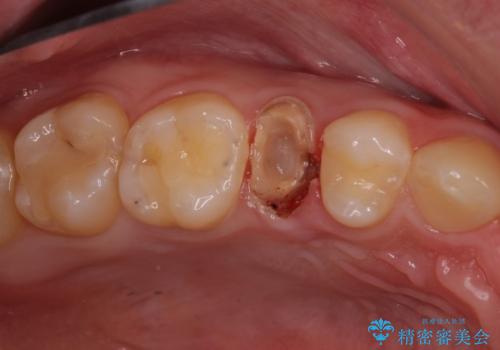

- 「左右どちらとも、どこかが痛む」とご来院された患者様です。

他院で虫歯治療を複数行っており、原因となりうる歯がいくつかありました。まずレントゲン上最もあやしい右上から治療開始しました。右上の歯は1本割れていたため、部分矯正で引っ張り出しました。

右上もう1本と左上は虫歯治療(セラミックインレー、セラミッククラウン)を行いました。

他院で虫歯治療を複数行っており、原因となりうる歯がいくつかありました。まずレントゲン上最もあやしい右上から治療開始しました。

右上の被せものを除去したところ、中で歯が割れていたため、部分矯正で引っ張り出すことになりました。